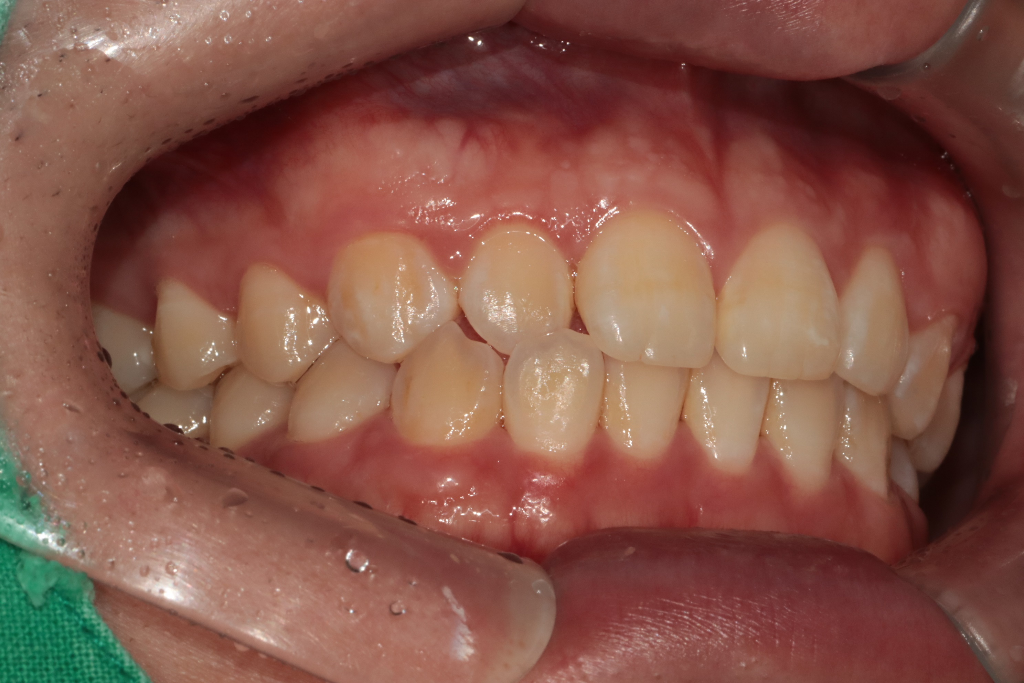

치아상태와 치아교합 위아래가 긴밀한가요?

치아 위아래교합이 긴밀한가요?

교정치료해야 하는 상태인가요?

치아상태가 긴밀하면 치아를 다물때 불편하나요?

치조골격문제로 긴밀해진건가요?

현재 치열 상태에서는 교정을 쉽게 권하지 않으며 치열이 양호한 편입니다. 다만 본인이 불편한 부위가 있다면 치과 방문 후 이에 대한 검사를 해보는 것이 필요합니다. 치열 자체는 정상적입니다.

-사진때문에 그런지는 몰라도 교합시 치아가 약간 깊게 물리는거 같습니다.

-긴민한것도 잇지만 오른쪽치아 쪽이 반대교합이 되고 있으니 교정을 상담해보세요.

-다물때자체는 크게 문제가 없지만, 긴밀한상태로 계속 지내다 보면 치아들이 힘을 많이 받기 때문에 예민해질수도 있습니다.

-골격의 문제도 있을수도 있고, 치아 배열등 다양한 원인에서 나타납니다.